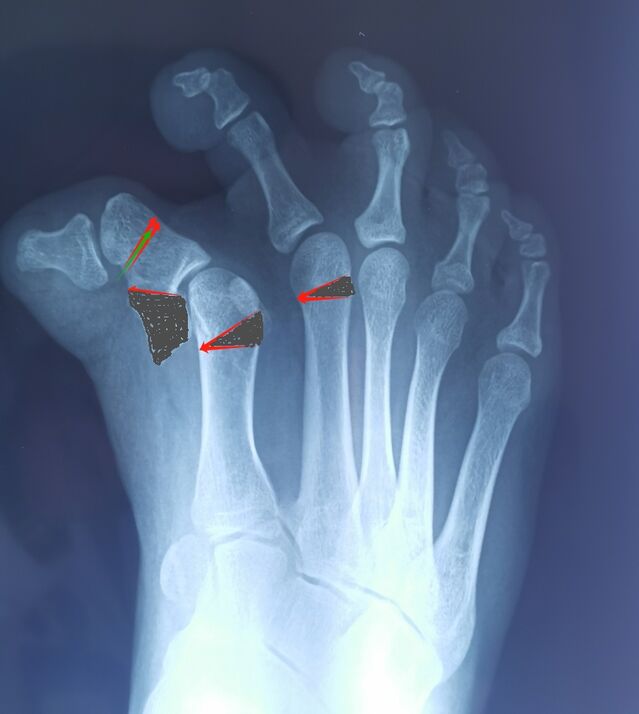

另一例足拇趾多趾畸形术后

微信图片_20240330000150.jpg